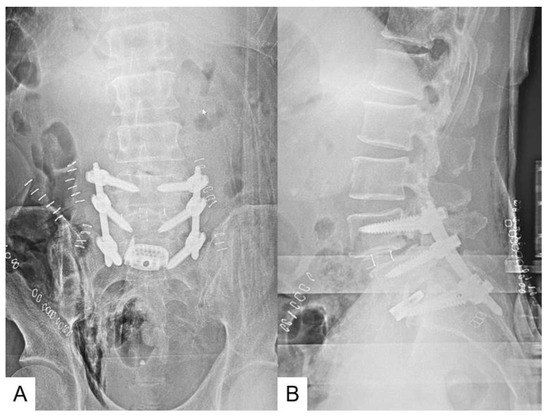

- Tanaka, M.; Sonawane, S.; Meena, U.; Lu, Z.; Fujiwara, Y.; Taoka, T.; Uotani, K.; Oda, Y.; Sakaguchi, T.; Arataki, S. Comparison of C-Arm-Free Oblique Lumbar Interbody Fusion L5-S1 (OLIF51) with Transforaminal Lumbar Interbody Fusion L5-S1 (TLIF51) for Adult Spinal Deformity. Medicina 2023, 59, 838. [Google Scholar] [CrossRef] [PubMed]

- Zygogiannis, K.; Tanaka, M.; Sake, N.; Arataki, S.; Fujiwara, Y.; Taoka, T.; Uotani, K.; Askar, A.E.K.A.; Chatzikomninos, I. Our C-Arm-Free Minimally Invasive Technique for Spinal Surgery: The Thoracolumbar and Lumbar Spine-Based on Our Experiences. Medicina 2023, 59, 2116. [Google Scholar] [CrossRef] [PubMed]

- Tan, Y.; Tanaka, M.; Sonawane, S.; Uotani, K.; Oda, Y.; Fujiwara, Y.; Arataki, S.; Yamauchi, T.; Takigawa, T.; Ito, Y. Comparison of Simultaneous Single-Position Oblique Lumbar Interbody Fusion and Percutaneous Pedicle Screw Fixation with Posterior Lumbar Interbody Fusion Using O-Arm Navigated Technique for Lumbar Degenerative Diseases. J. Clin. Med. 2021, 10, 4938. [Google Scholar] [CrossRef] [PubMed]